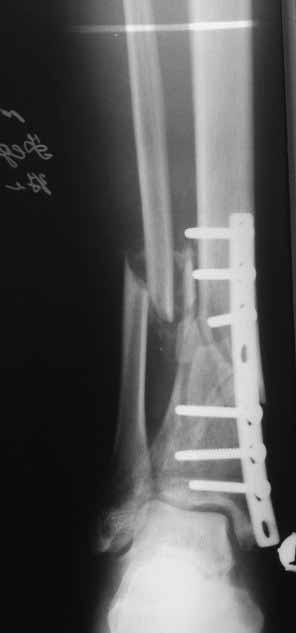

Да уж! Ни один из 3-х оперативных методов предшествующего лечения не был исполнен правильно. Везде был серьезный брак. Хотя любой из методов вполне мог бы и должен был бы привести к сращению,...если бы, да кабы.. В результате имеем то, что имеем. Что делать? Во-первых - подумать. Во-вторых - еще раз подумать. В третьих - еще больше подумать.

Иван, Вам видится зона перелома мертвой, а мне вовсе нет. Есть ли возможность сделать сцинтиграфию с технецием? Это может доказать нежизнеспособность или воспаление концов. Тогда есть резон для такой "крайней" меры как резекция. Есть ли клинические признаки инфекции в области первичной раны?, п\операционных рубцов?, в местах проведения спиц (нет ли спицевого остеомиелита)?.. В общем, вопросов может быть много.

Если нет данных за инфекцию в зоне перелома мы бы аппараптом дозированно устранили деформацию и, не удаляя дистальный фрагмент сломанного гвоздя, закрыто, после рассверливания заштифтовали бы достаточно толстым и надлежащей длины гвоздем.... Если есть спицевой остеомиелит, то также сначала аппарат, затем рассверливанме и цементный спейсор с а\б согласно посевам, через 2-3 недели удалить спейсор, повторно рассверлить и заштифтовать штифтом, возможно покрытым антибиотиком. А если Вы умело владеете техникой Илизарова, и больной согласен, можете оставить аппарат как окончательный метод фиксации....

В любом случае, если нет инфекции в зоне несращения и кость жизнеспособна, упаси Вас Бог что либо открывать и добавлять свободную костную пластику. Надо попытаться все сделать закрыто. Если откроете, то через пару месяцев, а может и раньше, все закончится резекцией и значительно большей чем 4 см...

Если там инфекция, что не исключено, судя по представленным данным, то вариантов нет - резекция в пределах здоровой кости.

Боюсь, кусок гвоздя в канале будет сильно мешать, так что мы бы открыли бы над ним передне-медиальную кожно-надкостнично-костную "крышку", и убрали. То есть не скелетировать чтобы кость даже вдали от несращения.

А так - согласен с Алексеем, аппаратная репозиция (если тугоподвижность - то за несколько дней), зону несращения не открывать, рассверлить, помыть, стержень с антибактериальным цементным покрытием.